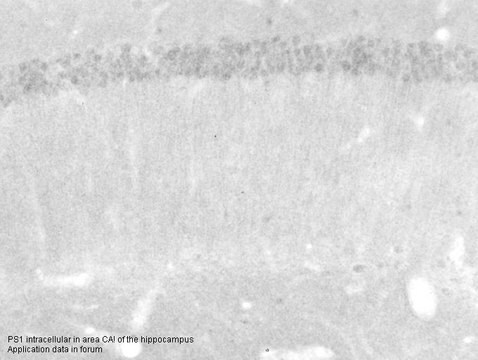

Anti-PSEN1 antibody produced in rabbit